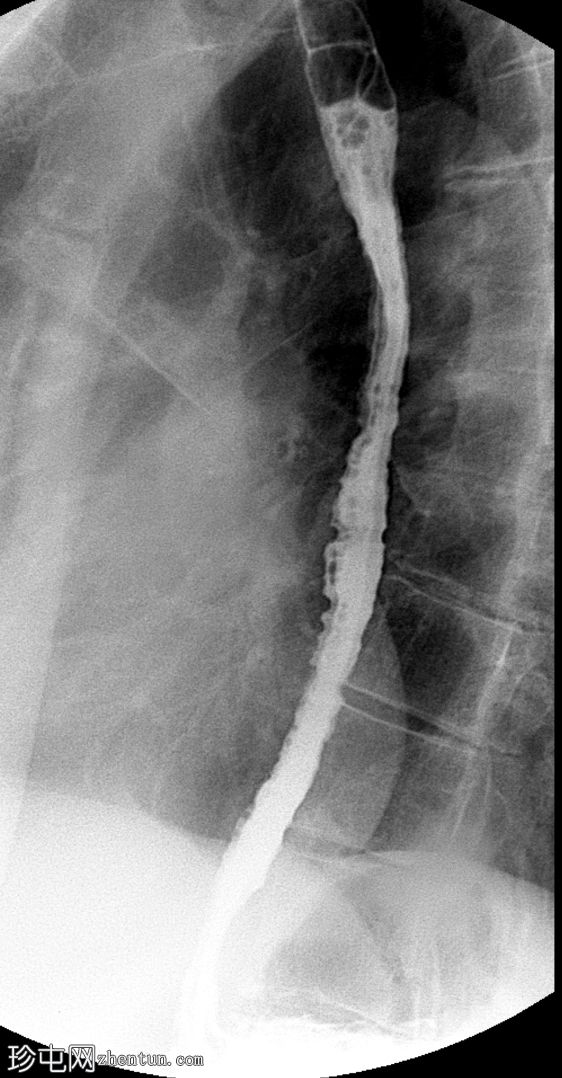

斜位

2.jpeg

可见一充满造影剂的、向后突出的憩室,位于咽食管交界处后壁,大致在T1椎体水平。憩室颈部狭窄,与颈段食管相通。吞咽时憩室充满造影剂,延迟显像显示造影剂滞留。食管其余部分管径和走行正常。未见远端梗阻。

Zenker 憩室是咽后壁的推进性(假性)憩室,起源于 Killian 裂隙。

表现为后正中线向外突出的囊状物,颈部狭窄,位于 T1(C5-C6)水平或略低于该水平。

钡餐侧位片显示最佳。